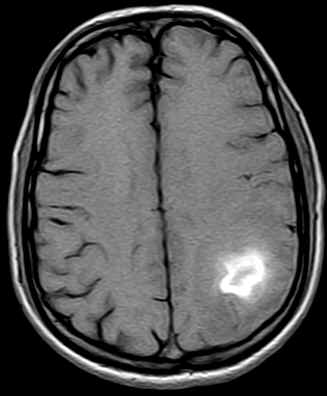

Diffuse hypointense areas on the T1W images which turn hyperintense on the Proton & T2W images are noted in the left parietal lobe. An area which is predominantly hypointense with a hyperintense rim on all sequences is noted in this lesion (subacute blood). The lumen of the superior sagittal sinus shows a hyperintense signal (no flow on the MRV-images not available) representative of a thrombus in this case.

·                     Hemorrhage may be present (20%).

·                     Gyral/Wedge shaped enhancement (32%).